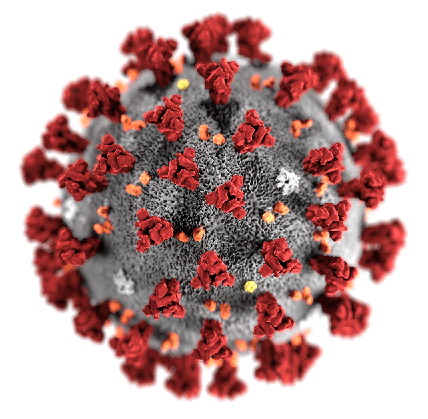

بارداری زمانی خاص و پر از هیجان و انتظار است. ولی برای مادران باردار شیوع بیماری کرونا، باعث شده که ترس، اضطراب و عدم اطمینان بر این اوقات خوش سایه بیافکند. بیماری کرونا یک بیماری ویروسی جدید است و تحقیقات درمورد آن همچنان ادامه دارد. به محض دریافت اطلاعات جدیدتر، این مقاله به روزآوری خواهد شد.

ما هنوز نمیدانیم که آیا ویروس حین بارداری از مادر به جنین منتقل می شود یا خیر. ویروس کرونا در مایعات واژن، خون بند ناف یا شیرمادر دیده نشده. با اینحال اطلاعات همچنان درحال بهروزرسانی است. ویروس کرونا تاکنون درمایع آمنیوتیک یا جفت نیز دیده نشده است.